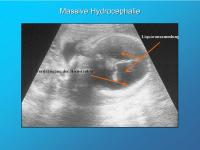

Massive Hydrocephalie

Abbildung 3

Keywords:

Hydrocephalie

Plexus chorioideus